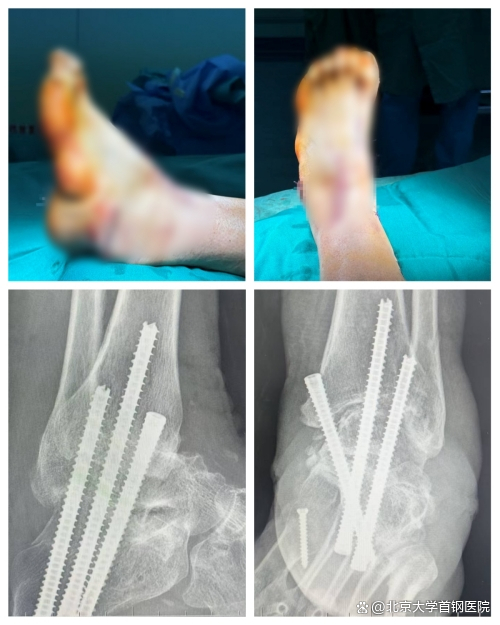

手术台上,无影灯照亮了李女士变形的足部,也照亮了创伤骨科团队专注的脸庞。切开皮肤,术中景象比术前检查更为严峻:踝关节胫骨及距骨关节面、跟骨及距骨关节面软骨布满磨损的痕迹,关节退变明显,重度关节炎让骨骼间的正常咬合关系荡然无存。主刀医生凝神聚力,先对挛缩的跟腱和跖筋膜进行松解,如同解开缠绕多年的绳结;随后在第一跖楔关节背侧做切口,精准实施楔形截骨,将低头的第一跖骨头巧妙抬高,如同为倾斜的“地基”重新找平;接着通过皮下隧道,将胫后肌腱用带线锚钉牢牢固定于外侧楔骨,完成肌腱平衡的关键一步;最后,将踝关节及距下关节固定于背伸90度的功能位,用3枚空心螺钉交叉固定,让关节融合在最佳角度,每一个动作都精准得如同绣花。

当纱布轻轻覆盖在术后的足部,一场历时数小时的“矫正之战”终于落下帷幕。拆线复查时,李女士迫不及待地看向自己的左脚:曾经蜷缩内翻的足部已恢复正常力线,高弓消失了,足跟归位了,脚踝也能自然活动。X光片上,清晰的骨骼排列见证着这场手术的成功。